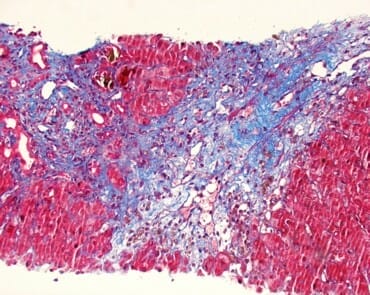

Stain results:

| 48 hours or more | Less than 48 hours | |

| Fibrin: | Bright Red | Orange to Orange-Red |

| Platelets | Gray blue to navy | Light Gray |

| Collagen: | Bright Blue | Bright Blue |

| Muscle: | Red | Red |

| Red Blood Cells: | Clear Yellow | Red, Green or Yellow |